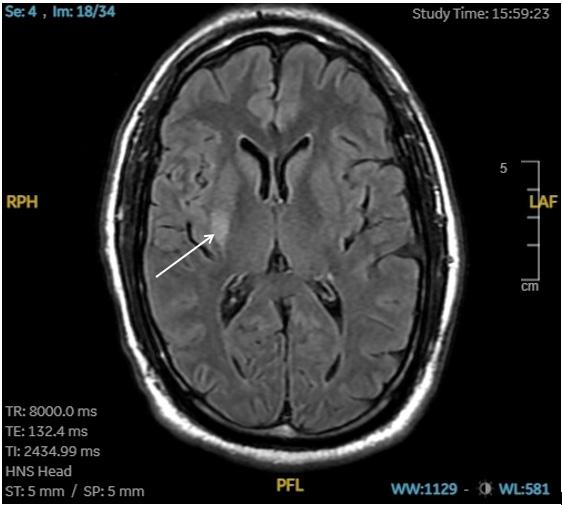

Neuroimaging, including computed tomography (CT) angiography of the head and neck and CT perfusion, revealed benign oligemia in the vertebral-basilar posterior circulation without evidence of penumbral regions or infarct core. The patient was then admitted to the intensive care unit for close monitoring. A magnetic resonance imaging study performed the following day identified an acute ischemic infarct in the right basal ganglia and insular region (Image). A follow-up CT conducted 24 hours later demonstrated hypodensity in the right putamen consistent with a subacute infarct.

Image. T2 FLAIR of magnetic resonance imaging brain revealing an acute ischemic infarct in the right basal ganglia and insular region (white arrow).

FLAIR, fluid-attenuated inversion recovery.